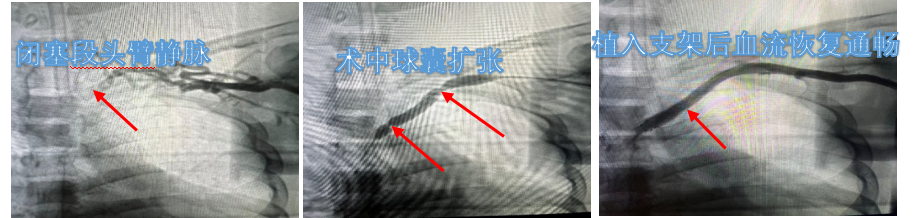

对于此类狭窄或闭塞患者,目前主要的治疗方式是微创介入,治疗目标是解除梗阻段,缓解症状,预防复发,术中采用局部麻醉方式,在超声定位下成功穿刺左腋静脉,导管导丝通过头臂静脉闭塞段后利用球囊扩张头臂静脉,再植入裸支架,术后造影见无名静脉血流显影,管腔通畅。对于部分介入治疗失败的病例,也可以考虑行手术取栓或行胸廓出口减压进一步解除血管的压迫。